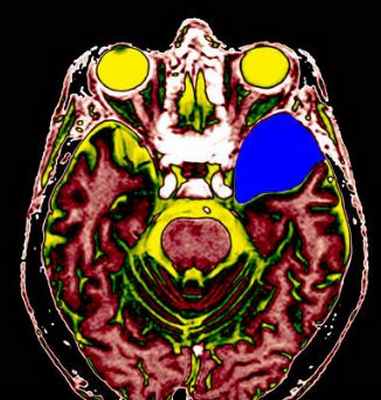

о Корональные Т2-ВИ: оценка взаимоотношения с хориоидальной щелью(а) МРТ, Т1 -ВИ, сагиттальный срез: определяется крупная киста хориоидальной щели, оказывающая масс-эффект на прилегающий гиппокамп.

Наиболее часто такие кисты являются случайно находкой, однако в данном случае сообщается о предположительной связи кисты с комплексными парциальными судорожными приступами.

(б) MPT, FLAIR, аксиальный срез: у этого же пациента тотчас позади крючка гиппокампа определяется изоинтенсивная киста хориоидальной щели.

Киста смещает височный рог бокового желудочка и деформирует нормальный гиппокамп. Кисты хориоидальной щели имеют ликворную интенсивность сигнала на всех последовательностях. (а) МРТ, Т2-ВИ, корональный срез: определяется киста хориоидальной щели, смещающая височный рог бокового желудочка и вызывающая сдавливание и деформацию гиппокампа и парагиппокампальной извилины.

МРТ головного мозга. Арахноидальная киста полюса левой височной доли. Цветовая обработка.